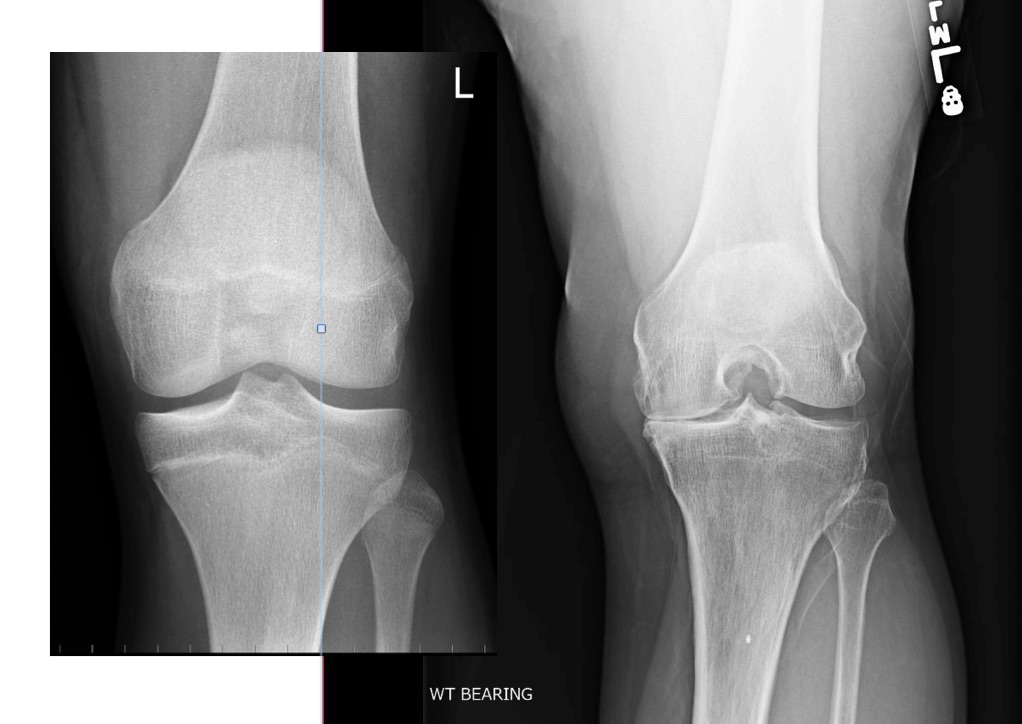

Comparison of my left knee pre-surgery, and the knee of a “normal” male, 36 years old. My knee, on the right, has bone on bone contact, bone dissolution due to knee-cap aggravation, and a wide gap on the left side due to long term adaptation to the irritation. The wide gap is common, and causes the development of a bow legged gait.

The goal of a full knee replacement is to remove damaged bone and replace it with new materials that allow the knee a full range of smooth motion. The picture above shows my left knee pre-operation; The femur and tibia are touching on the left side and all the cartilage is gone. That constant contact has caused a gap in the bones on the right side – this is one of the body’s adaption mechanism to the pain. Unfortunately, it also changes the biomechanics of leg motion, and caused my leg to become “bow legged”. Finally, the constant contact of the patella on the knee sans cartilage has prompted some bone dissolution giving the knee an a appearance of limestone fossil. Several figures above this text is the x-ray of my replaced right knee; the damaged areas have been cut away and replaced with metal and flexible cushion constructed of polyethylene.